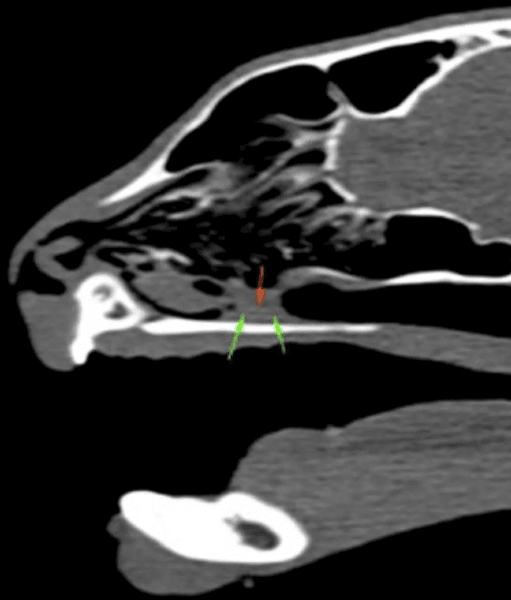

Ветеринары были удивлены после того, как обнаружили, что сильное чихание было вызвано тоненьким растением длиной 10 см. Рентген подтвердил, что травинка заблокировала ноздрю животного.

Ренгтен подтвердил, что травинка заблокировала ноздрю животного

"Нам пришлось использовать компьютерную томографию и эндоскоп, представляющий собой длинную гибкую камеру, чтобы полностью увидеть, что происходит, поскольку в левой носовой полости была густая слизь, а также наблюдался отек мягких тканей. Когда мы обнаружили, что это была травинка, мы удалили ее с помощью специальных щипцов, и я рада сообщить, что Лео хорошо восстановился и теперь наслаждается дополнительными лакомствами и прогулками дома", — сказала она.